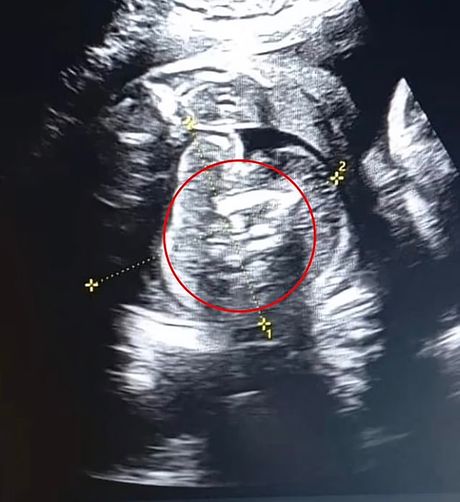

Prošlog meseca, 32-godišnja žena otišla je u lokalnu bolnicu na rutinski ultrazvučni pregled dok je bila u 35. nedelji trudnoće. Iako su prethodni pregledi bili uredni, lekari su u stomaku nerođenog dečaka primetili „dodatnu strukturu sa kostima“.

Dalja ispitivanja otkrila su da su unutar fetusa postojala još dva malformisana fetusa.

Oba fetusa su razvila ruke i stopala, ali nisu imala potpuno formirane vitalne organe, zbog čega nisu mogli da prežive samostalno.